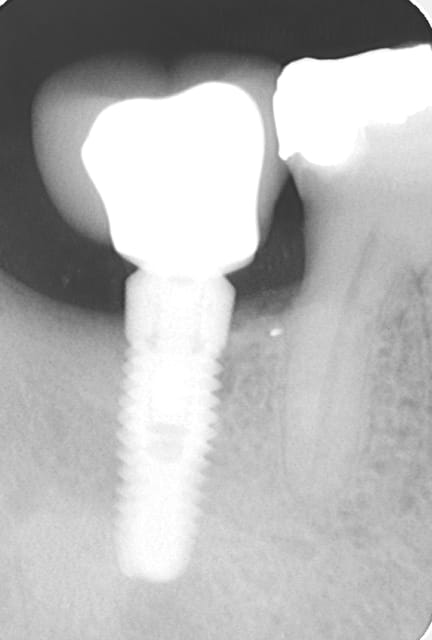

Voici 2 clichés radiologiques qui peuvent paraître surprenants (ici c'est un implant easyimplant à connexion type astra), le premier en juillet 2009 le jour de la pose de la couronne et le deuxième ce mois d'août 2011 (certes vous êtes obligé de me croire, mais ce n'est pas la première fois que j'observe ce phénomène). Ici, le patient procède à un contrôle de plaque parfait.

> Voici 2 clichés radiologiques qui peuvent paraître surprenants (ici c'est un

> implant easyimplant à connexion type astra), le premier en juillet 2009 le jour

> de la pose de la couronne et le deuxième ce mois d'août 2011 (certes vous êtes

> obligé de me croire, mais ce n'est pas la première fois que j'observe ce

> phénomène). Ici, le patient procède à un contrôle de plaque parfait.

Et bien moi je te crois tout à fait: l'os a tendance à croitre du fait de la stimulation et cela nous est caché (presque toujours) par l'agression bactérienne chronique, c'est ce que je crois.

growly vraiment super tes 2 radios